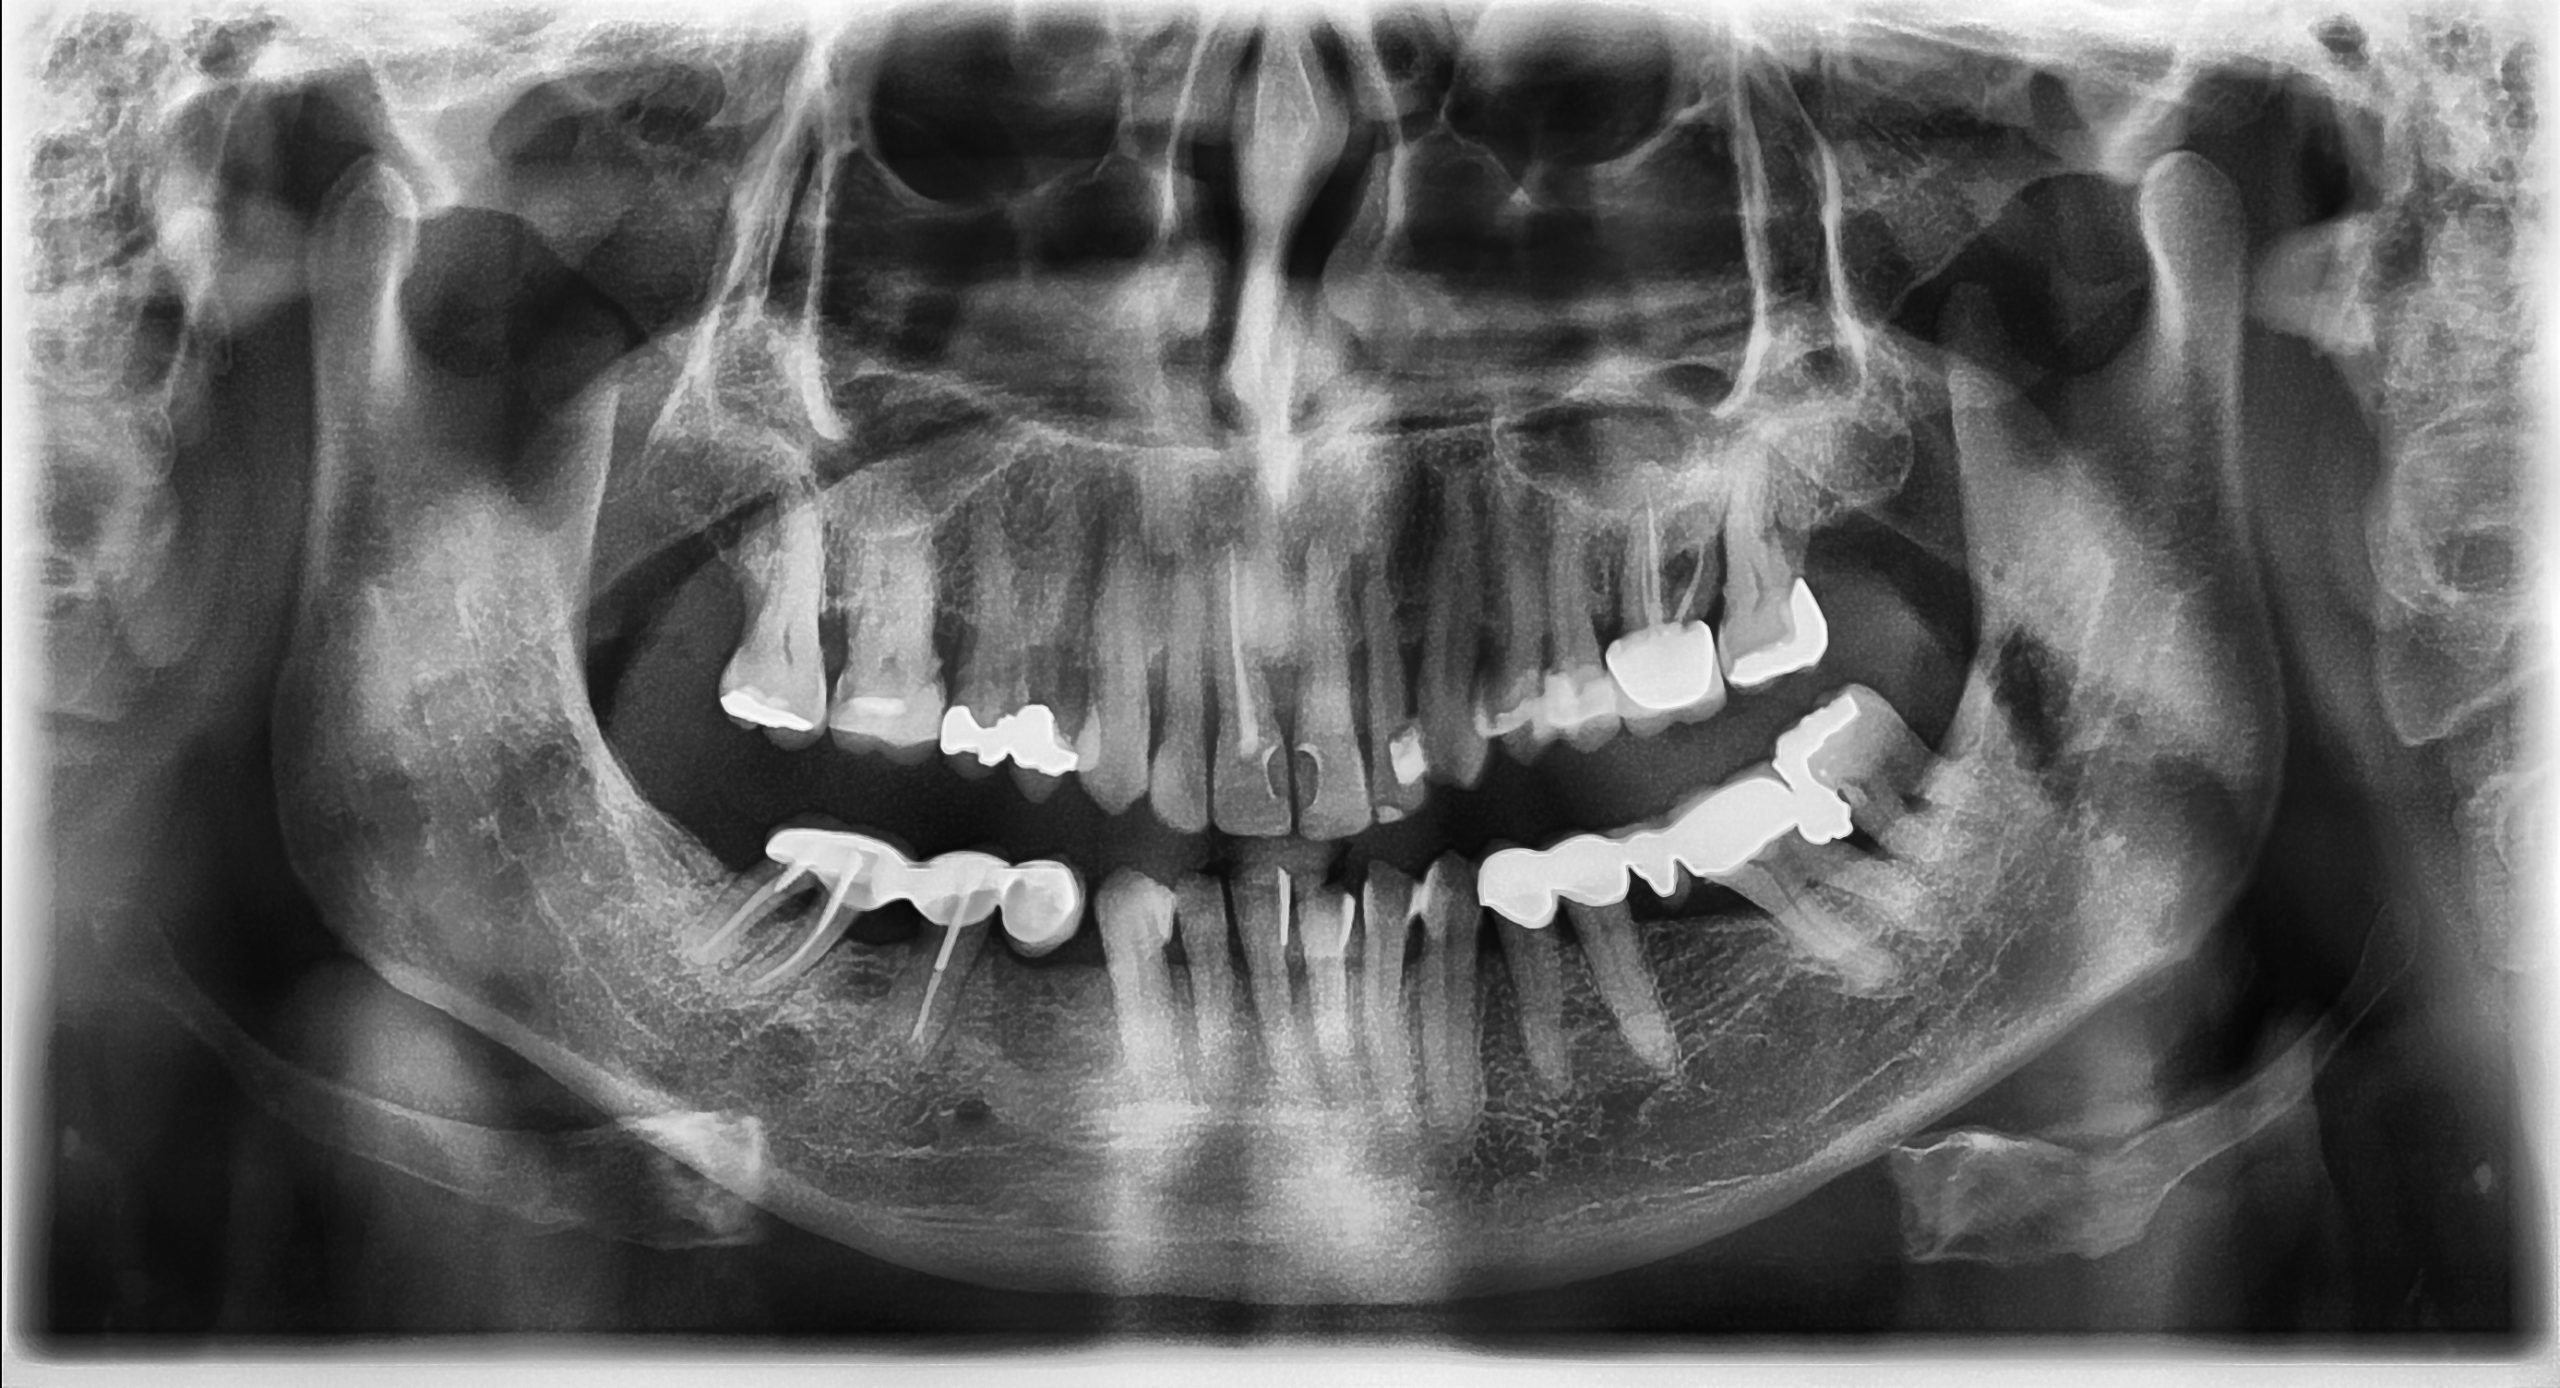

Restore appearance and function to your smile

Do you have missing, damaged, or painful teeth and long for a fully functioning and confident smile? From innovative dental implants to bespoke crowns and bridges, we’ve got you covered. Trust our expert restorative dental care to give you the results you’ve been dreaming of - book your restorative consultation today!